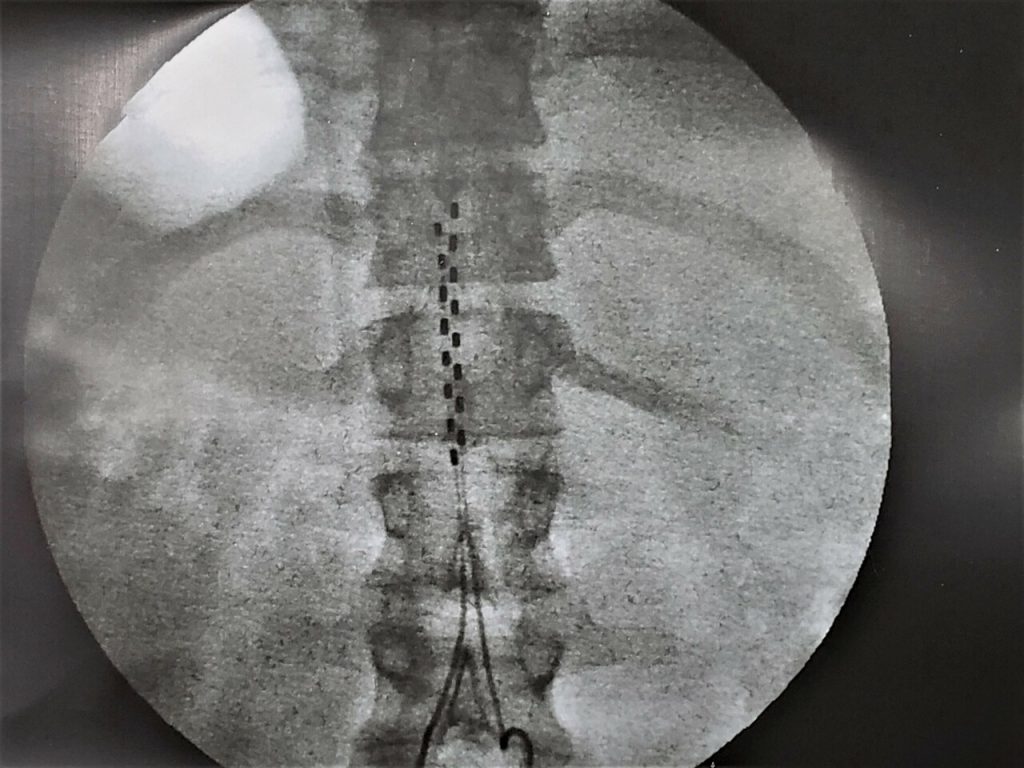

- Radiografia do pós-operatório de Implante de Neuroestimulador Medular (Eletrodo em Placa 16 contatos).